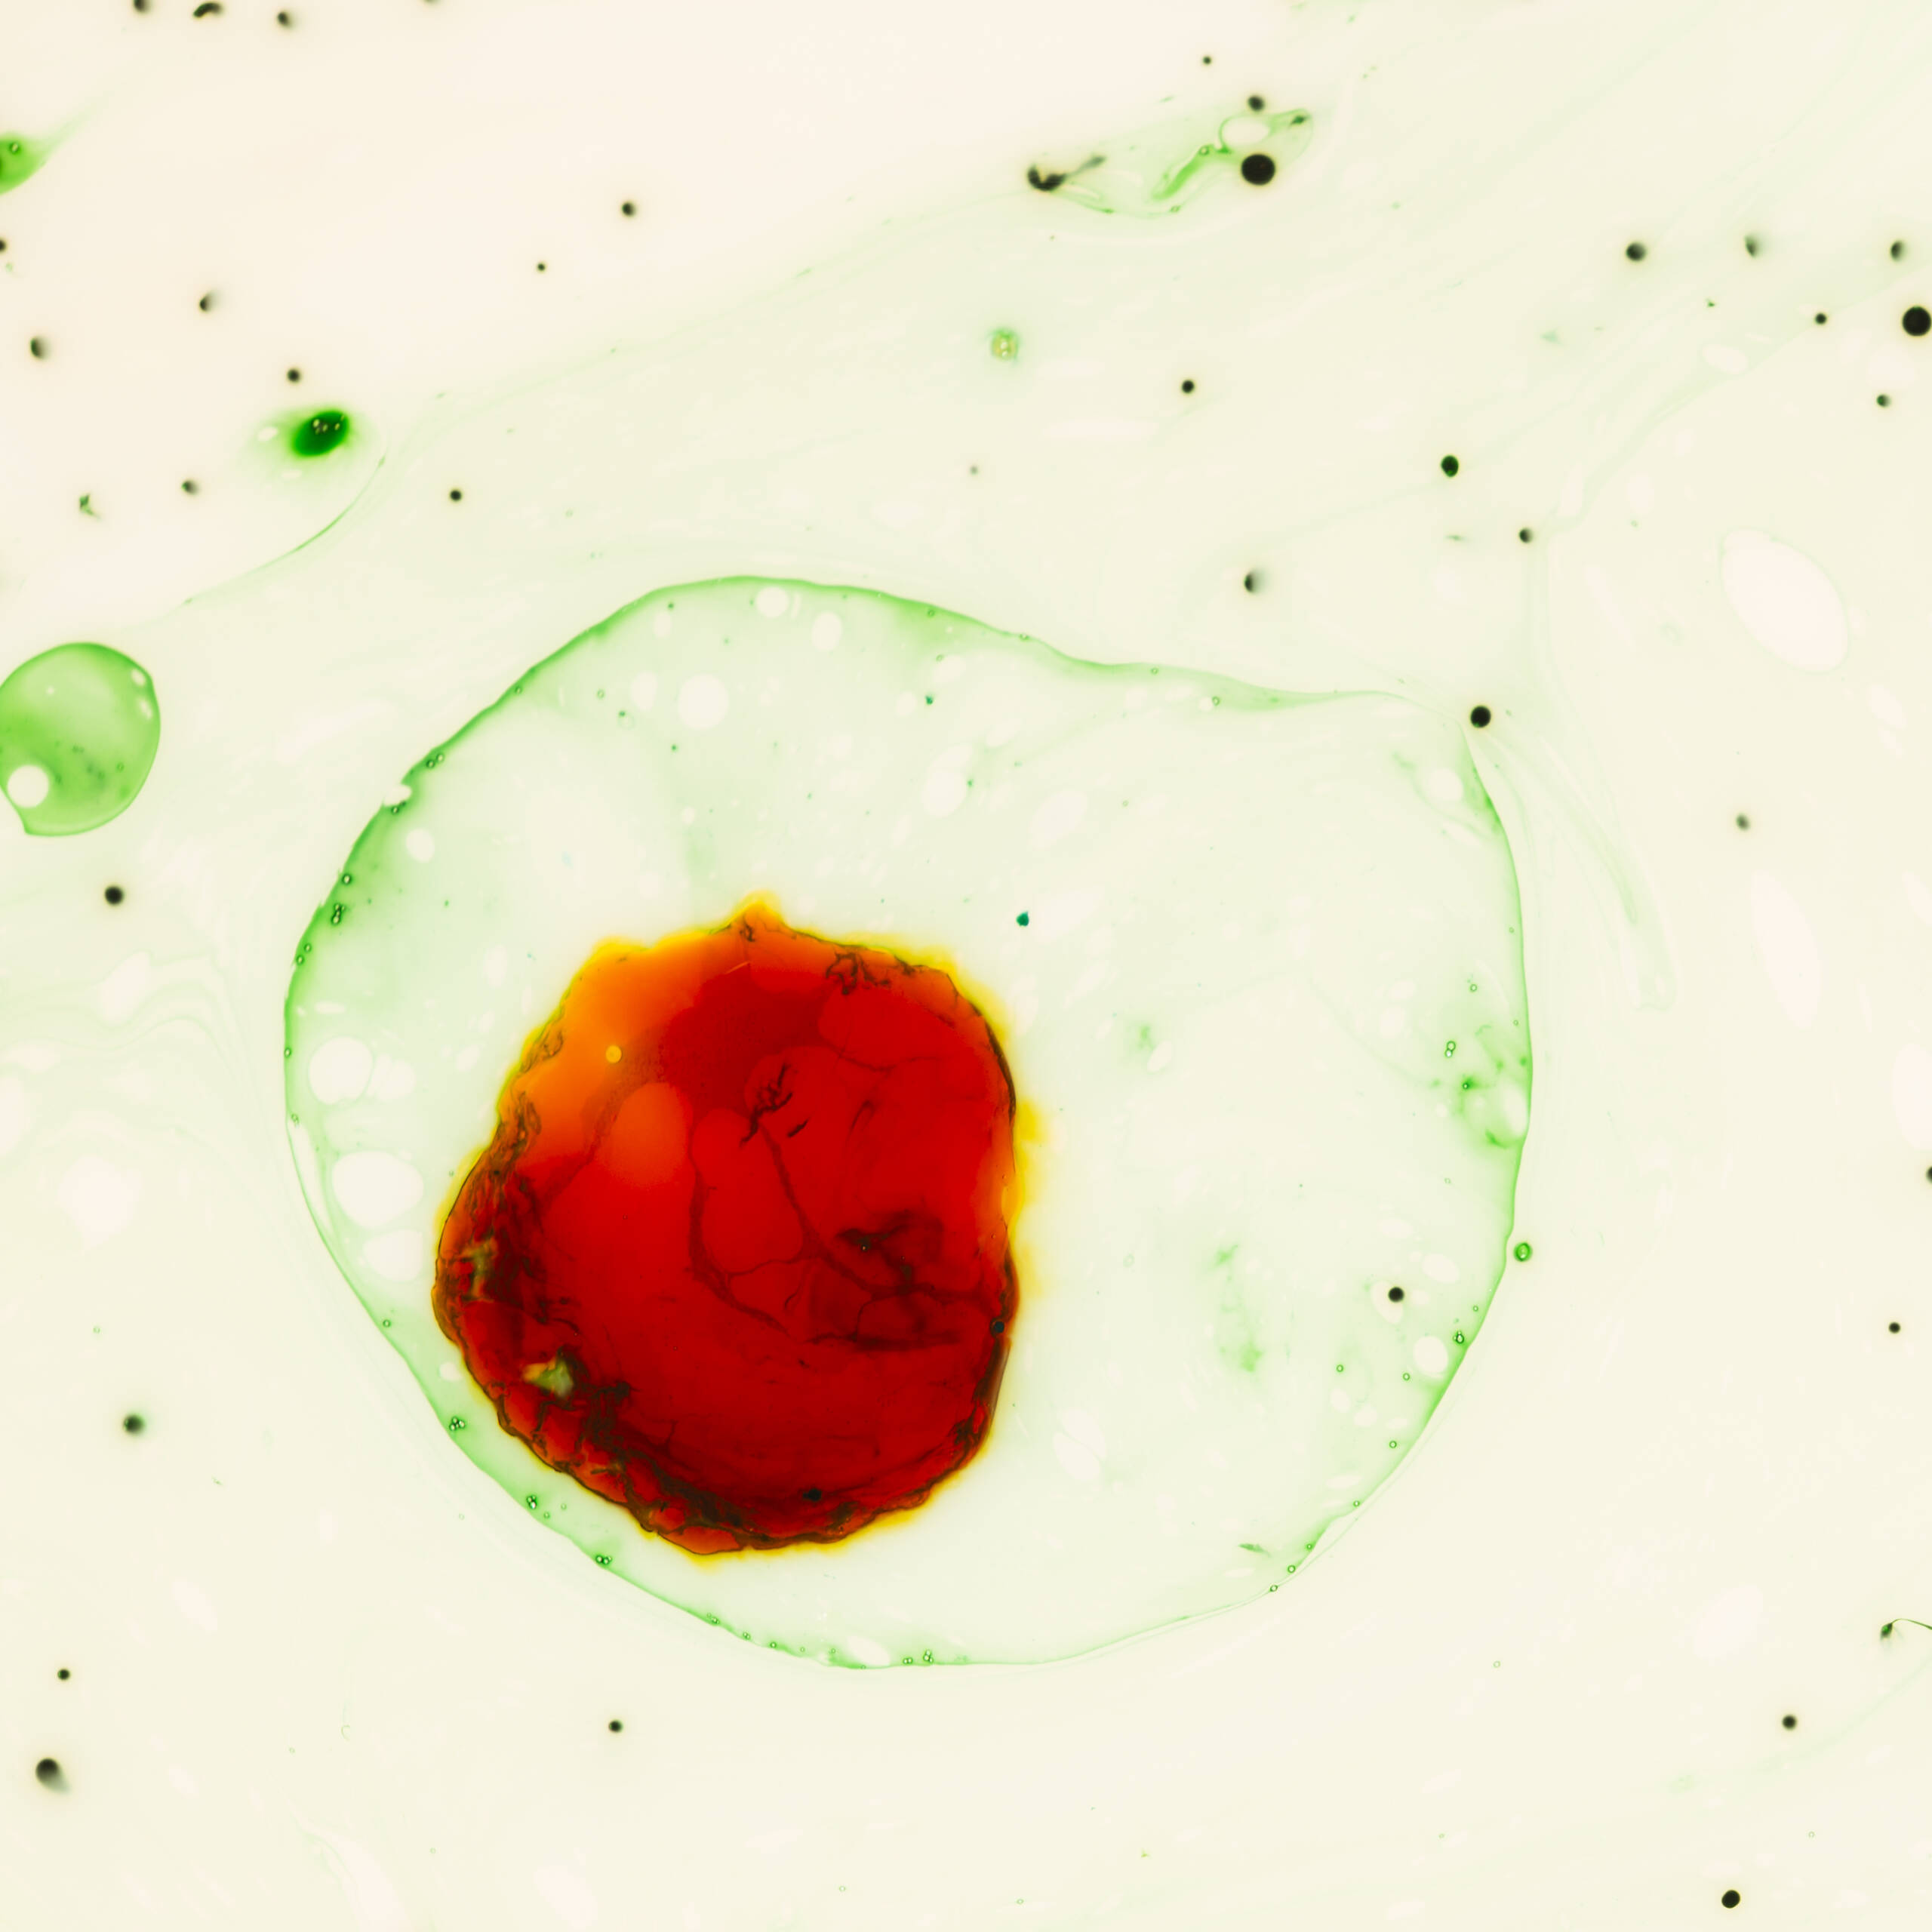

The researchers found changes in the quantity, size, volume, and function of red blood cells in the population exposed to mercury contamination, which can lead to anaemia. Changes in other biomarkers also indicate damage to organs such as the liver and kidneys. Mercury was found to increase triglyceride levels, which are a risk factor for cardiovascular disease. Additionally, creatinine and urea levels were high in the contaminated population, suggesting kidney dysfunction.